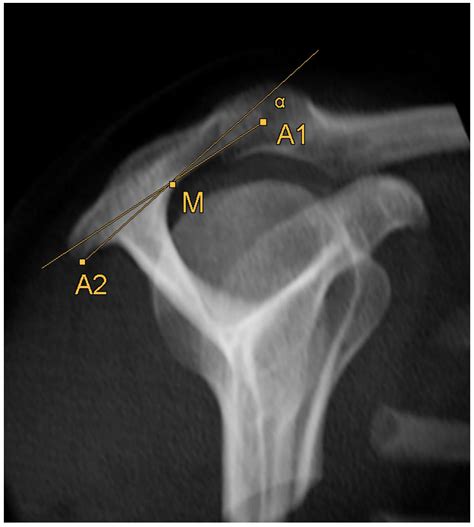

Diagnosing Acromion Types

Diagnosing the type of acromion typically involves a combination of physical examination and imaging studies. Radiographs (X-rays) are commonly used to visualize the shape of the acromion. Magnetic Resonance Imaging (MRI) and Computed Tomography (CT) scans can provide more detailed images of the shoulder joint and surrounding structures, aiding in the diagnosis of acromion types and associated conditions.